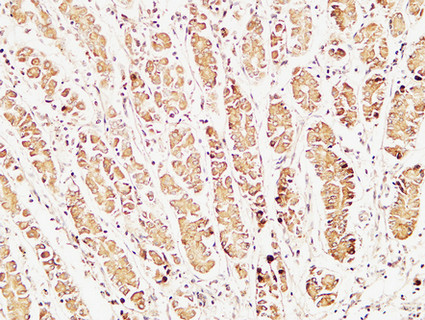

Product Image

| IHC | 1/50-1/100 |